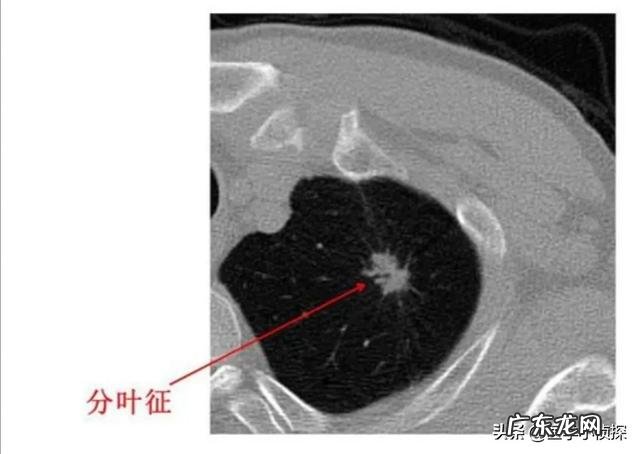

而且拍片发现肺结节 , 本身不能说我们得了什么病 , 因为肺结节只是我们影像学上的一种表现 , 并不代表这个结节具体会是个什么东西 。只是对于我们正常人来说 , 不应该有结节 , 因此结节的出现肯定代表我们的肺部有病变 , 但具体它是什么 , 是良性的 , 还是恶性的 , 需要进一步的来区分 。只不过 , 一般情况下 , 在影像下我们统称这些都叫肺结节 。